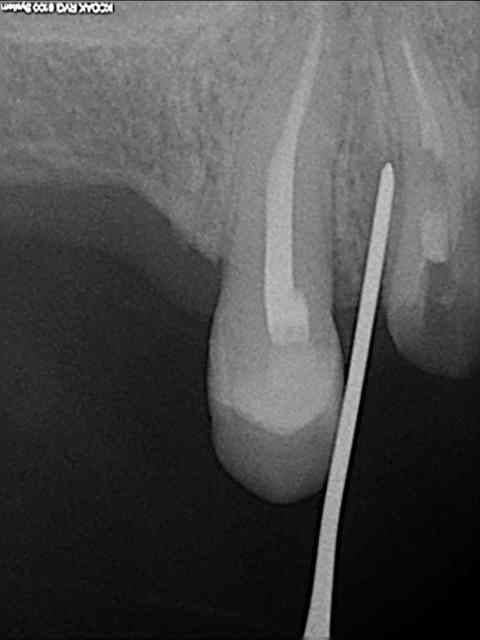

aussitôt demandé, aussitôt fait !!

(j+1 an)

tu as perdu pas mal d'os!!